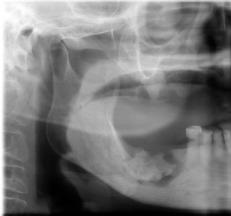

1.吸烟影响拔牙创血凝块的稳定

拔牙创的愈合关键点之一在于良好的创口封闭,封闭的关键在于拔牙窝内的血凝块。拔牙创内充满的血液约于15~30分钟即可形成血凝块而将创口封闭。此血块的存在有保护创口、防止感染、促进创口正常愈合的功能。吸烟时口腔内会形成负压环境,这样的环境下很容易把拔牙创内的血凝块吸出来,从而出血不止。

3.吸烟烟气中热量对于口腔组织潜在损伤

一支香烟在点然后可以产生700~1000℃的高温,其烟气也带有大量的过高温度。这些温度虽高,但相较于口腔内大面积的粘膜组织和唾液面积还是小的多,且存在时间短,温度才不至于灼伤口腔。但是拔牙后拔牙窝牙槽骨直接暴露于口腔,这一瞬间的温度足以造成骨灼伤甚至骨坏死。大量的高热刺激骨组织可以使得骨发生坏死、感染。